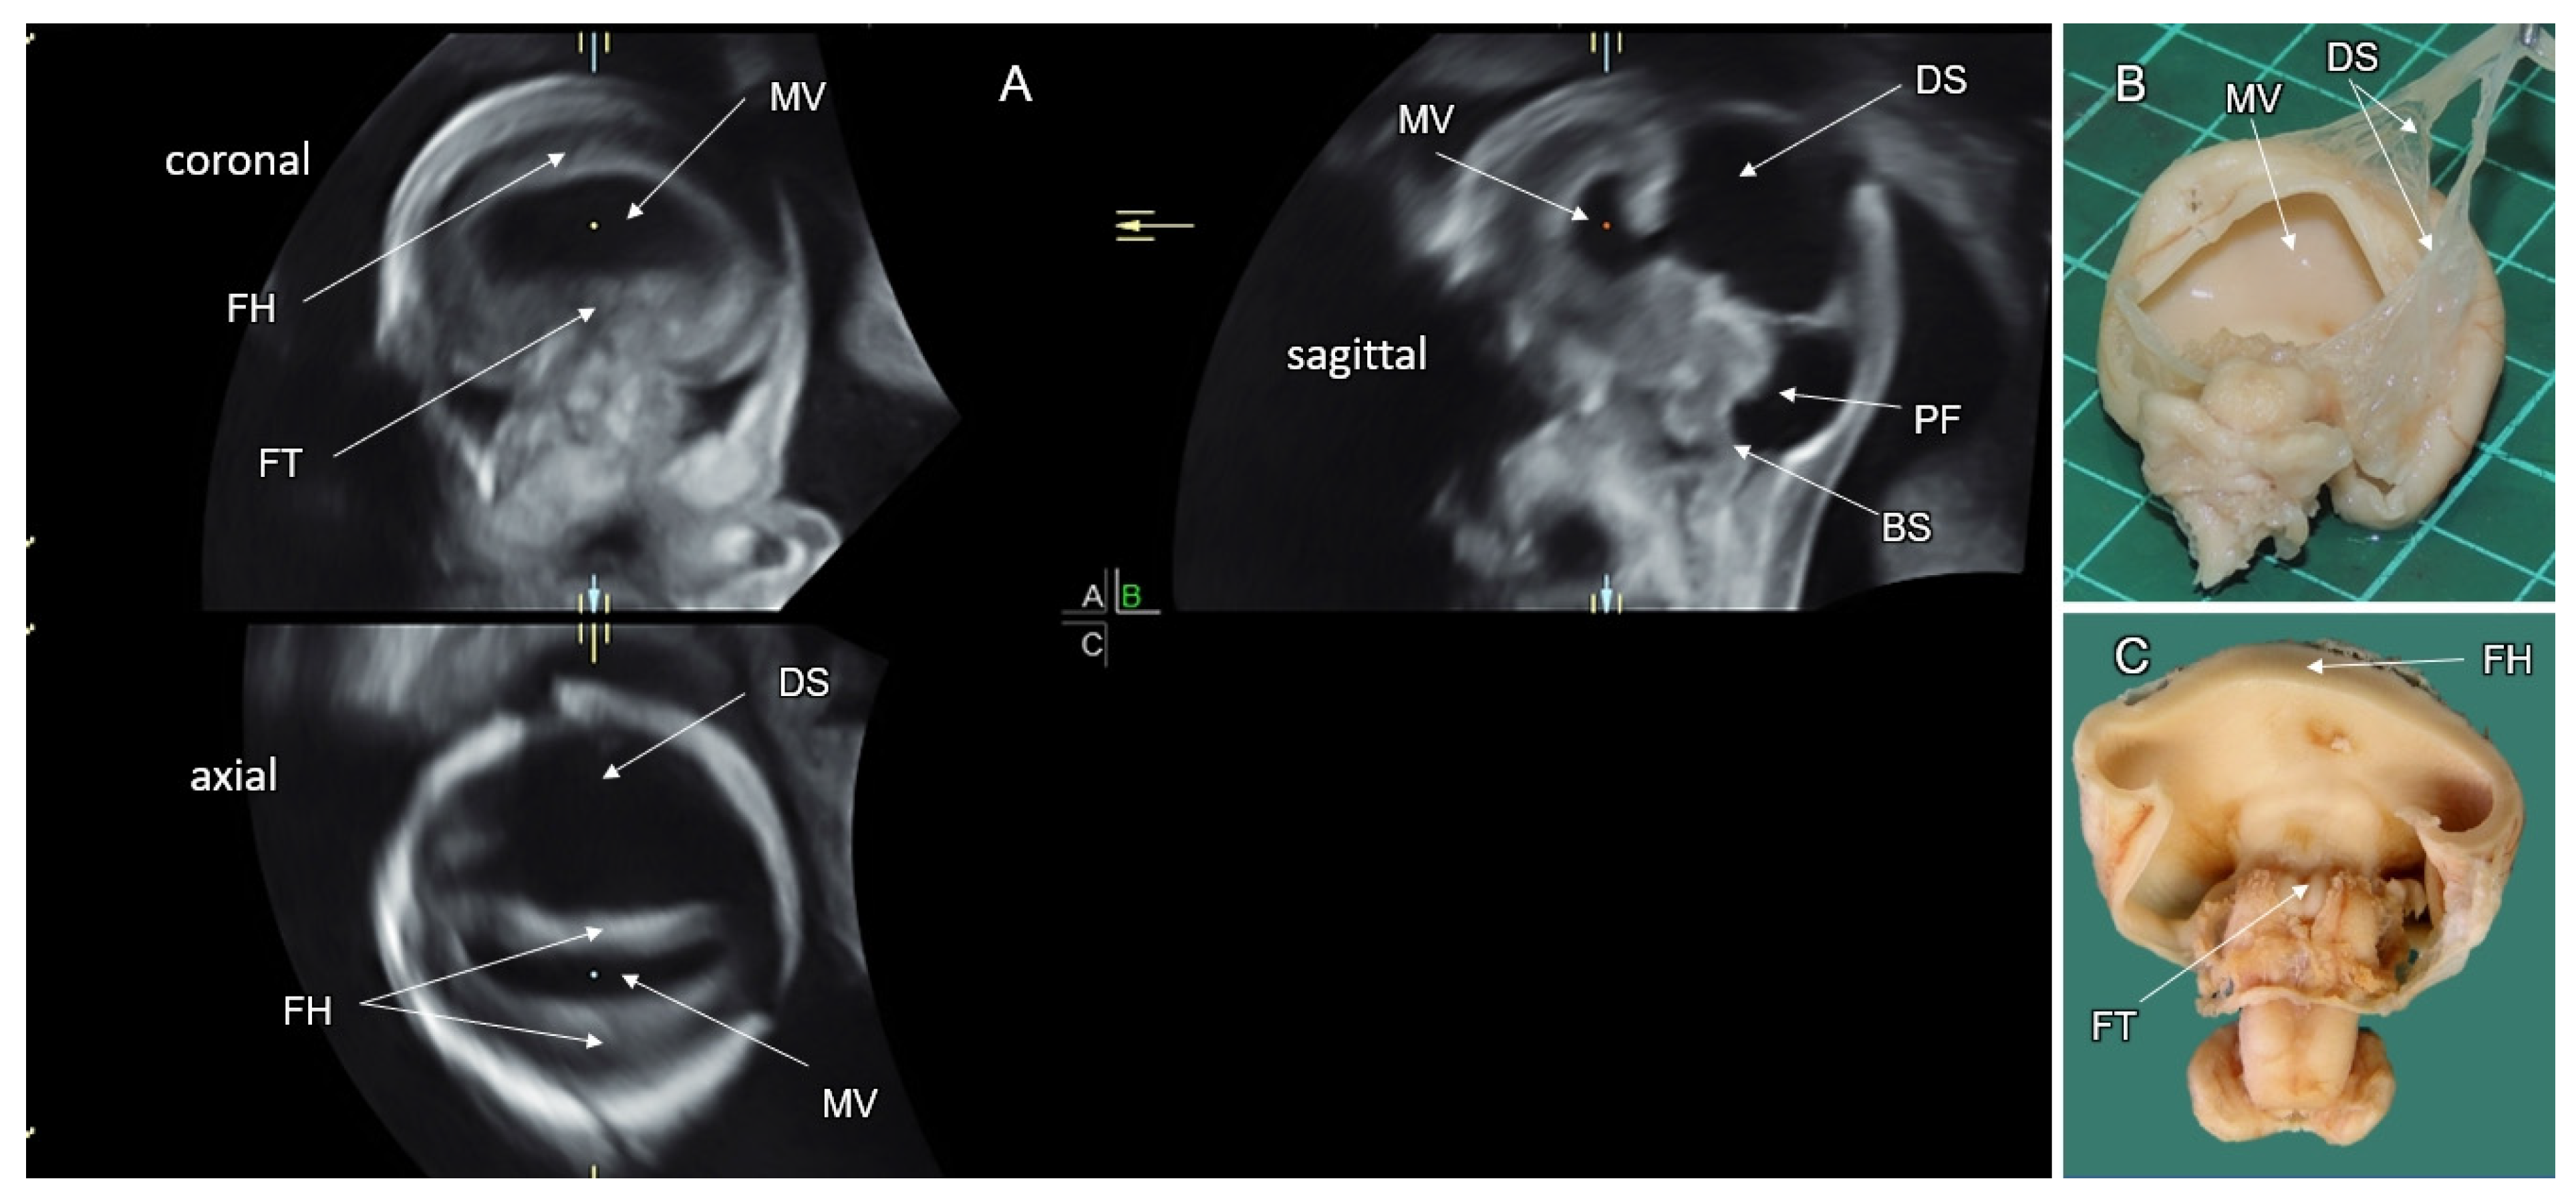

7.6. Rhombencephalosynapsis (RES)